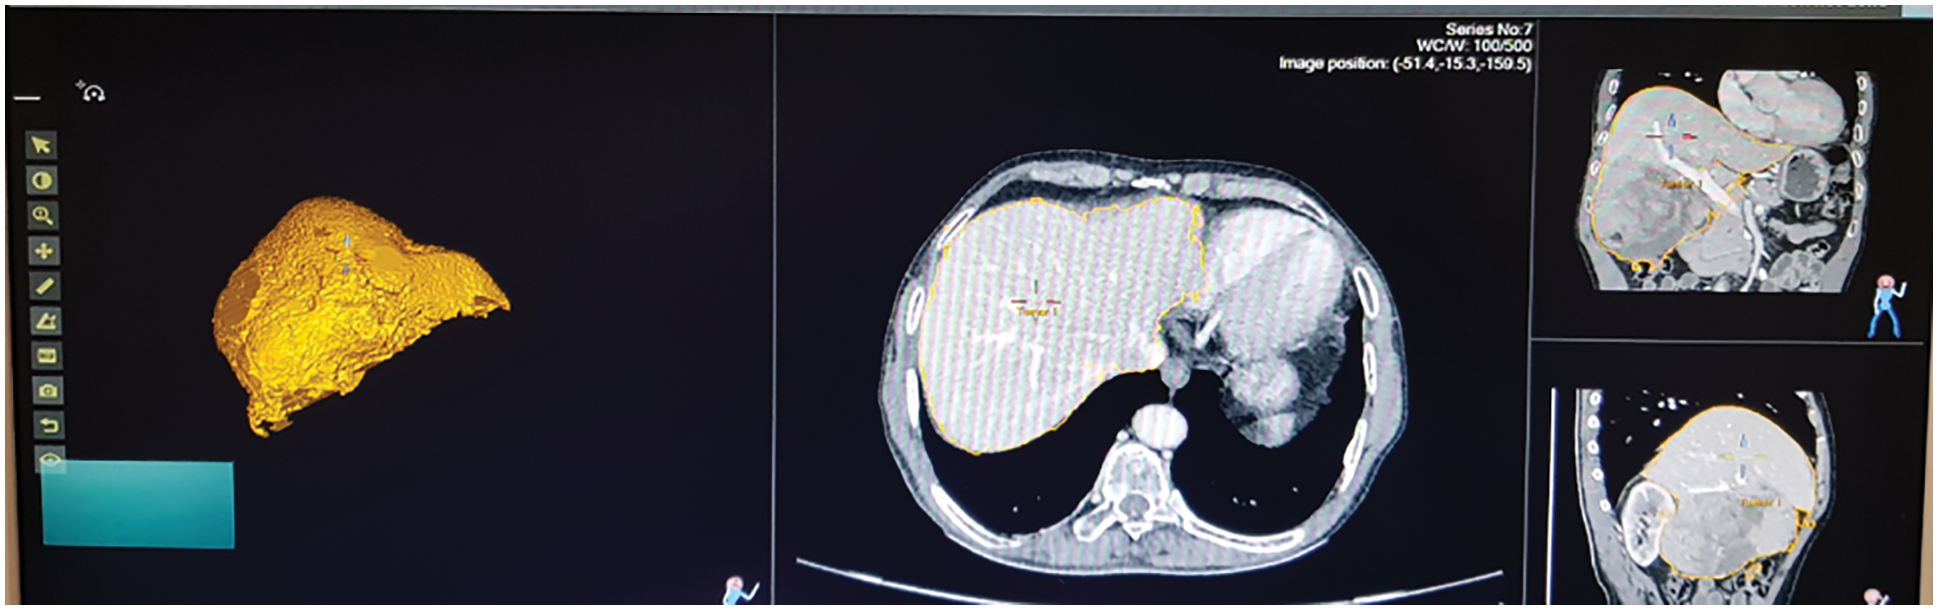

Fig. 13 shows the ultrasound value of medium fatty liver patient. The total liver volume is 1467 cc, right liver volume is 445.9 cc and left liver volume is 1021.88 cc. The medium fatty liver signal obtained from male patient age 70. Fig. 14 shows the ultrasound of mild fatty liver patient. The total liver volume is 961.86 cc, right liver volume is 365.93 cc and left liver volume is 595.33 cc. The mild fatty liver male patient at age 70. The signals from fatty liver are obtained from fatty liver sensor for sever mild and moderate fatty liver patients. The statistical parameters of the fatty liver signal from TQWT and the ultrasound lab values are correlated using gaussian regression modelling.

Figure 13: Ultrasound of medium fatty liver patient